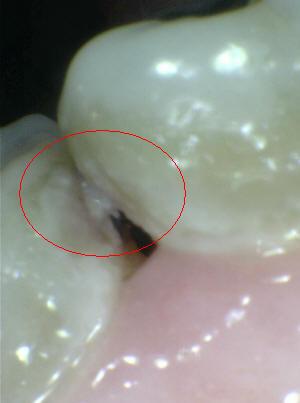

¿Determine los códigos pertinentes a cada imagen?

Click en el hipervínculo: Para comparar el resultado de su diagnóstico